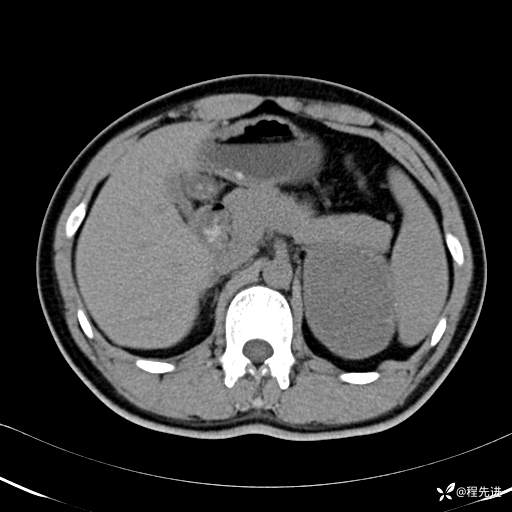

【腹盆】特别精彩病例|体检发现的左侧腹膜后占位期待您的精彩解读

呱呱叫了 等 3 位达人已点赞患者性别:男

患者年龄:25岁

简要病史:体检发现

CT平扫:(CT值:平扫,27HU,动脉期,27HU,门静脉期,31HU,平衡期,32HU)

CT增强:

动脉期: